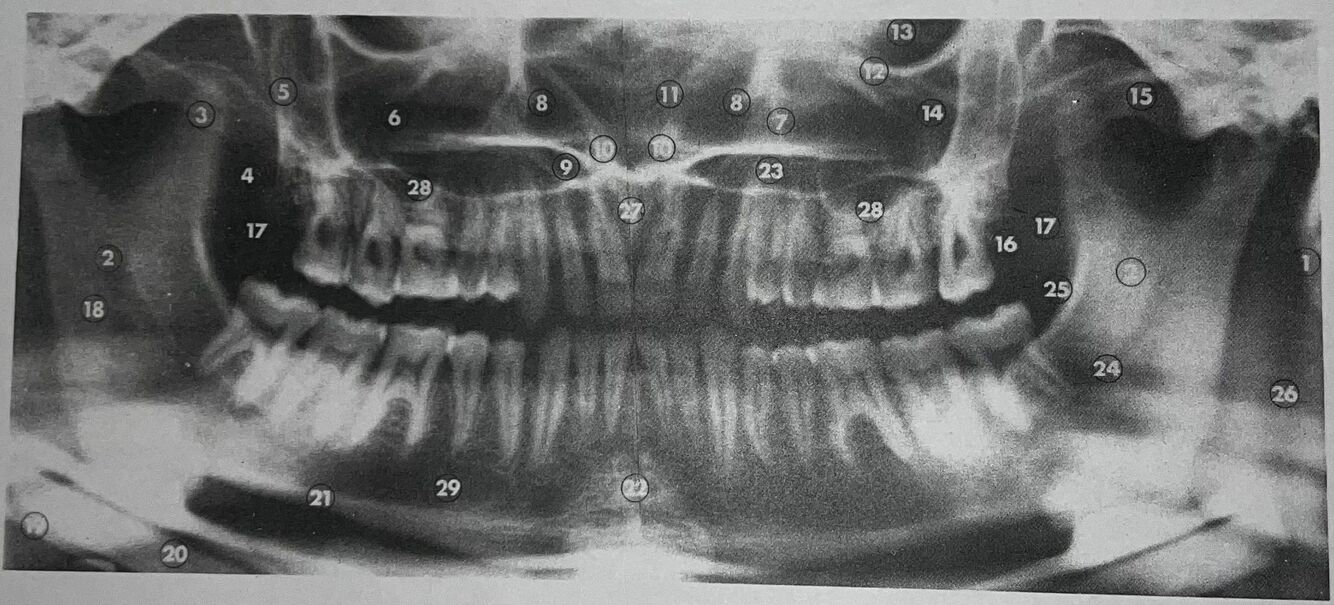

what is 1

mastoid process

what is 2

what is 3

coronoid process

what is 4

lateral pterygoid plate

what is 5

posterior wall of antrum

what is 6

antrum (maxillary sinus)

what is 7

anteromedial wall of antrum

what is 8

inferior concha

what is 9

floor of nasal fossa

what is 10

anterior nasal spine

what is 11

nasal septum

what is 12

infraorbital ridge

what is 13

orbital cavity

what is 14

malar process

what is 15

zygomatic arch

what is 16

maxillary tuberosity

Q

what is 17

what is 18

what is 20

inferior border of mandible

what is 22

mental protuberance

what is 23

23

A

mandibular canal

what is 25

internal oblique line

what is 26

superimposition of right jaw

what is 27

incisive canals

what is 28

floor of antrum

what is 29

mental foramen